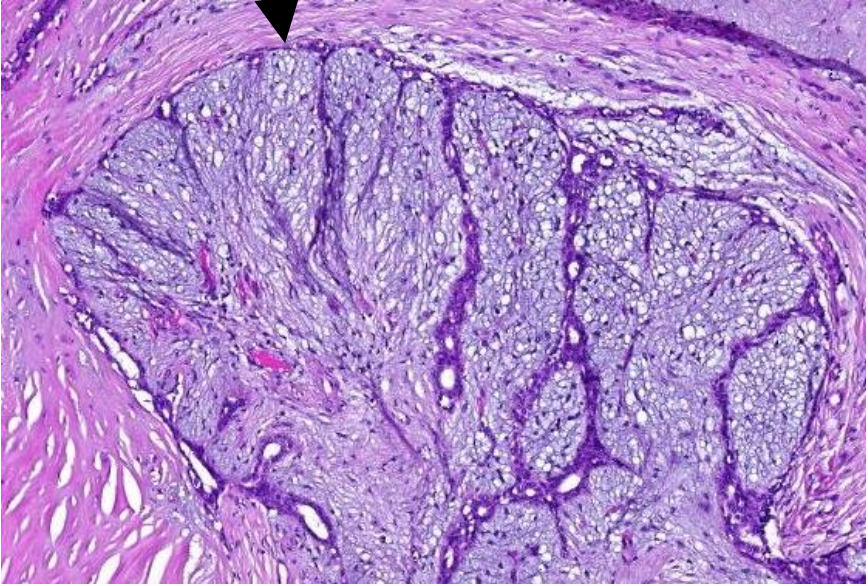

welk preparaat

levercirrose met macrovesiculaire steatose

benamingen van boven naar beneden (levercirrose)

kapsem van Glisson

Hepatocyten

Bindweefsel

chronische ontsteking lever gevolgen

fibrose en verlies hepatocyten

—> nodules

= cirrose

histologische tekens van ontsteking lever

toename in sclereus bindweefsel

ganaalkanaaltjes

vascularisatie